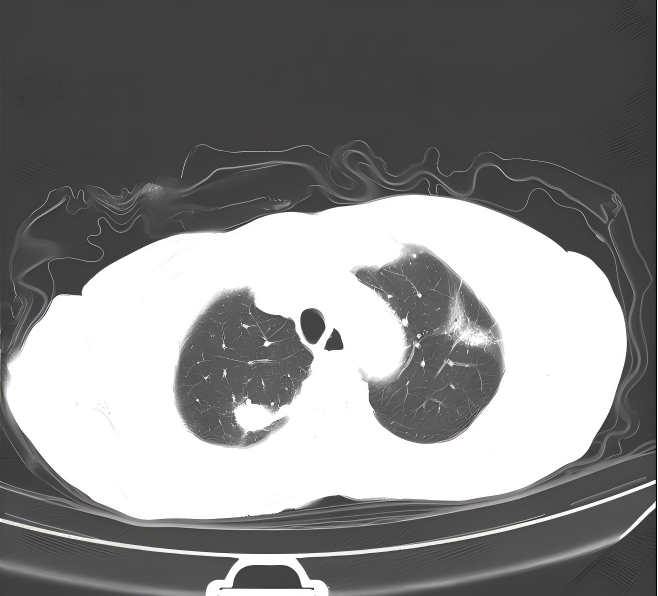

胸部+上腹部增强CT:2023.12.04我院门诊肺部CT示:1.左肺上叶结片影;右肺上叶及右肺门结块,右肺门形态增大,右肺下叶部分支气管截断,多考虑肿瘤性病变,请结合临床病史及对比前片。2.右侧胸腔积液;伴右下肺膨胀不全。3.扫及肝脏囊性灶;胆囊结石。

1、胸水引流和灌注化疗:于2023.12.04 行右侧胸腔积液穿刺引流术,引流出约1500m1淡红色胸水,送检细胞学可找到肿瘤细胞。于12.08 、12.15行2次顺铂(40mg)胸腔灌注化疗,过程顺利,未诉不适。复查胸部CT提示胸水消失。

OoCNxjw6Pe2NhnUiFbeWjYFJJF3cHziA.png

CT.jpg1.png2.png3.png